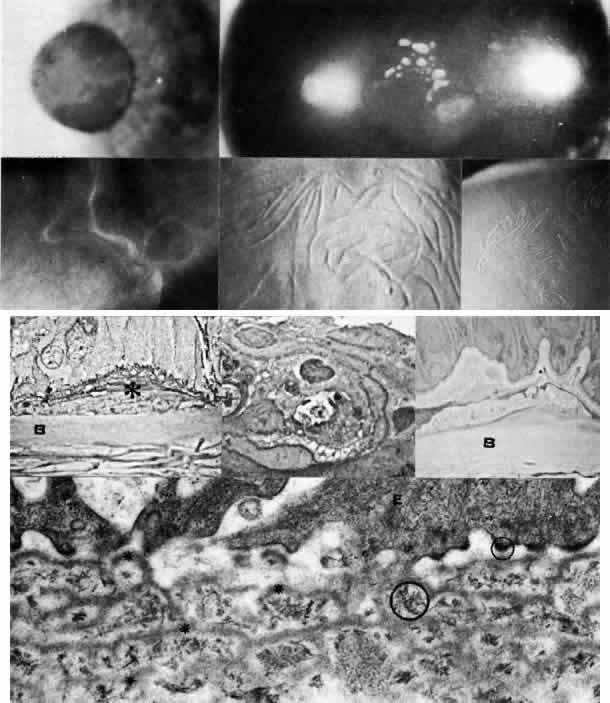

Granular Dystrophy (Groenouw Type I)

Granular dystrophy is manifested in the first decade of life and is transmitted as an autosomal dominant trait. The lesions are sharply demarcated, milky, opaque figures resembling snowflakes or bread crumbs and are confined to the axial portion of the cornea, usually beginning in the most superficial portion of the stroma (Figs. 5 AND 9; Color Plate 1F). During their evolution, they may extend more posteriorly. Between the dense opacities the intervening cornea is characteristically clear. Variants with confluent central opacities and epithelial involvement have been described.98

Fig. 9. Granular corneal dystrophy. Top left. Discrete, large opacities predominantly affect the central stroma. Top right. Retroillumination emphasizes the optical clarity of intervening stroma between granular opacities. Middle left. Light microscopy of hyaline deposits is accentuated with Masson trichrome stain (× 250). Right. Transmission electron micrograph shows relatively normal epithelium (E) and basement membrane (arrowheads) anterior to large electron-dense deposits (*) within Bowman's layer and stroma (× 4,500). Bottom left. Higher magnification transmission electron micrograph of granular deposits shows characteristic rod-shaped paracrystalline structure ( × 50,000). (Top right, Slit lamp photograph courtesy of Lawrence Hirst, MD)

Jones and Zimmerman99 noted the opacities to consist of areas of hyaline degeneration in which stromal fibers appeared “granular.” Histologically, the deposits stain red with Masson trichrome stain and are less PAS-positive and less birefringent than the normal stroma. Numerous argyrophilic fibers are seen on Wilder's reticulin stain. Using histochemical techniques, Garner100 concluded that the deposits consisted mainly of noncollagenous protein containing tryptophan, arginine, tyramine, and sulfur-containing amino acids, and he postulated that the abnormal proteins originated from the epithelium, keratocytes, and extracorneal sources. Rodrigues and co-workers101 found immunofluorescent evidence of microfibrillar protein, a poorly characterized glycoprotein, as well as a Luxol fast blue-staining phospholipid. Johnson and co-workers suggest an epithelial origin of the deposits based on light and electron microscopic studies of corneas with recurrent granular dystrophy.102 On transmission electron microscopy, the deposits appear as extracellular, rod-shaped, electron-dense paracrystalline structures with faintly visible periodicity. Keratocytes, endothelium, and Descemet's membrane appear unaffected.103

Lattice Dystrophy

Lattice dystrophy is an autosomal dominant condition characterized by pathognomonic, branching “pipestem” lattice figures within the stroma (Figs. 5 AND 10; Color Plate 1G). Symptoms usually begin in the first decade of life and include decreased vision as well as recurrent erosions because of subepithelial and stromal accumulations of amyloid material. In time, the condition progresses to involve marked opacification of the axial stroma, as well as in the superficial layers, leaving the limbus relatively free. At this stage, since the cornea also shows a superficial haze, it becomes difficult to visualize typical lattice lesions, and hence examination of younger affected family members is useful. Amyloid accumulation under the epithelium gives rise to poor epithelial-stromal adhesion with consequent recurrent erosion syndrome.49 The dystrophy advances inexorably, and by age 40 or earlier these problems become markedly aggravated, causing considerable discomfort and visual incapacity.

Fig. 10. Lattice corneal dystrophy. Top. Slit lamp photograph demonstrates pathognomonic branching lattice figures throughout the stroma. Middle left. Phase-contrast photomicrograph shows subepithelial accumulations of fibrillar amyloid deposits (*) causing distortion of epithelial contour. B, Bowman's layer (paraphenylenediamine, × 800). Middle right. Transmission electron micrograph of basement membrane complexes reveals basement membrane irregularity and discontinuity resulting from underlying amyloid fibrils (× 21,000). Bottom left. Transmission electron micrograph of stroma shows normal collagen fibrils and keratocytes with electron-dense material abnormally dispersed extracellularly (× 16,000). Bottom right. High-magnification transmission electron micrograph resolves lattice material as masses of fine, 8- to 10-nm diameter amyloid fibrils (circled below) in comparison with larger-size stromal collagen fibrils (above) (× 75,000). (Slit lamp photographs courtesy of WJ Stark, MD)

Many published reports have documented the nature of the corneal deposits in lattice dystrophy. In 1961, Jones and Zimmerman99 and others suggested that the disorder was due to amyloid degeneration of the stromal collagen fibers. In 1967, Klintworth111 confirmed that the disorder was a familial form of amyloidosis limited to the cornea and showed that the fibrillar material stained with Congo red and exhibited the birefringence and dichroism typical of amyloid. On transmission electron microscopy, the fine, electron-dense fibrils of 8 to 10 nm diameter are similar to those of known amyloid fibrils. Using fluorescence microscopy, staining with thioflavin-T is helpful in further characterizing the amyloid material, as are immunofluorescent studies using antihuman amyloid anti-sera.112 Evaluation of corneas with typical lattice dystrophy has demonstrated the presence of the amyloid P (AP) component, but staining for amyloid A (AA) protein has remained controversial.113–117 The corneal endothelium and Descemet's membrane are not involved. Moreover, amyloid deposits have not been found in other excised tissues from patients with typical lattice dystrophy.111

Macular Dystrophy (Groenouw Type II)

Among the classic corneal dystrophies, macular dystrophy, unlike granular and lattice dystrophies, is an autosomal recessive disorder and is far less common. It usually begins in the first decade of life and leads to progressive visual deterioration as the stroma becomes generally cloudy, with superimposed dense, gray-white spots (Figs. 5 AND 11; Color Plate 1H). Unlike granular dystrophy, these macular spots have indefinite edges and the intervening stroma is not clear. Young patients exhibit axial lesions in the superficial layers of the cornea, but with time, lesions approach the periphery and extend throughout the entire stromal thickness. Corneal thinning confirmed by central pachymetry has been documented.129 Also unique is primary involvement of the endothelium as evidenced clinically by the presence of guttate changes of Descemet's membrane.

Fig. 11. Macular corneal dystrophy. Top left. Clinical appearance of cornea features diffuse haze extending to the limbus with superimposed, dense gray-white spots. Bottom left. Light photomicrograph of posterior cornea shows endothelial cells staining intensely positive for acid mucopolysaccharide. Guttate excrescences (*) of Descemet's membrane (DM) are frequent. The stroma also shows positive staining for acid mucopolysaccharide both diffusely extracellularly and intensely within keratocytes (circled) (colloidal iron × 500). Right. Transmission electron micrograph discloses typical fibrillary granular deposits within keratocytes (K), throughout the posterior layer of Descemet's membrane, and within the endothelial cells (En). The anterior banded region of Descemet's membrane (bracketed) is not affected (× 3500).

The lesions in macular corneal dystrophy stain intensely with alcian blue and colloidal iron, minimally with PAS, and not at all with Masson's trichrome. Birefringence is decreased. The lesions have been histochemically identified as an abnormal keratan sulfate-like glycosaminoglycan that accumulates extracellularly within the stroma and Descemet's membrane and intracellularly within keratocytes and endothelium.130

As would be typical of an autosomal recessively inherited condition, macular dystrophy presumably results from deficiency of a hydrolytic enzymes (sulfotransferase) and may thus be considered a localized mucopolysaccharidosis.131 The effect of altered glycosaminoglycan metabolism is evident at the cellular level; on transmission electron microscopy, keratocytes and endothelial cells exhibit distention of rough-surfaced endoplasmic reticulum cisternae. With the acridine orange technique, compensatory generalized hyperactivity of the lysosomal enzyme system has been demonstrated.132 Eventually the accumulated undigested storage products engorge the cells, and the cells ultimately degenerate or rupture. The derivation of these intracytoplasmic storage vacuoles from endoplasmic reticulum suggests that the biochemical lesion in macular dystrophy occurs at a different metabolic location than in the systemic mucopolysaccharidoses, since in the latter, storage products accumulate within lysosomelike intracytoplasmic vacuoles associated with the Golgi complex.133 Snip and associates134 were able to determine that the storage phenomenon affecting endothelium and Descemet's membrane is likely also primary, since the intracellular and extracellular lesions appear ultrastructurally comparable to those evident in the keratocytes and stroma.